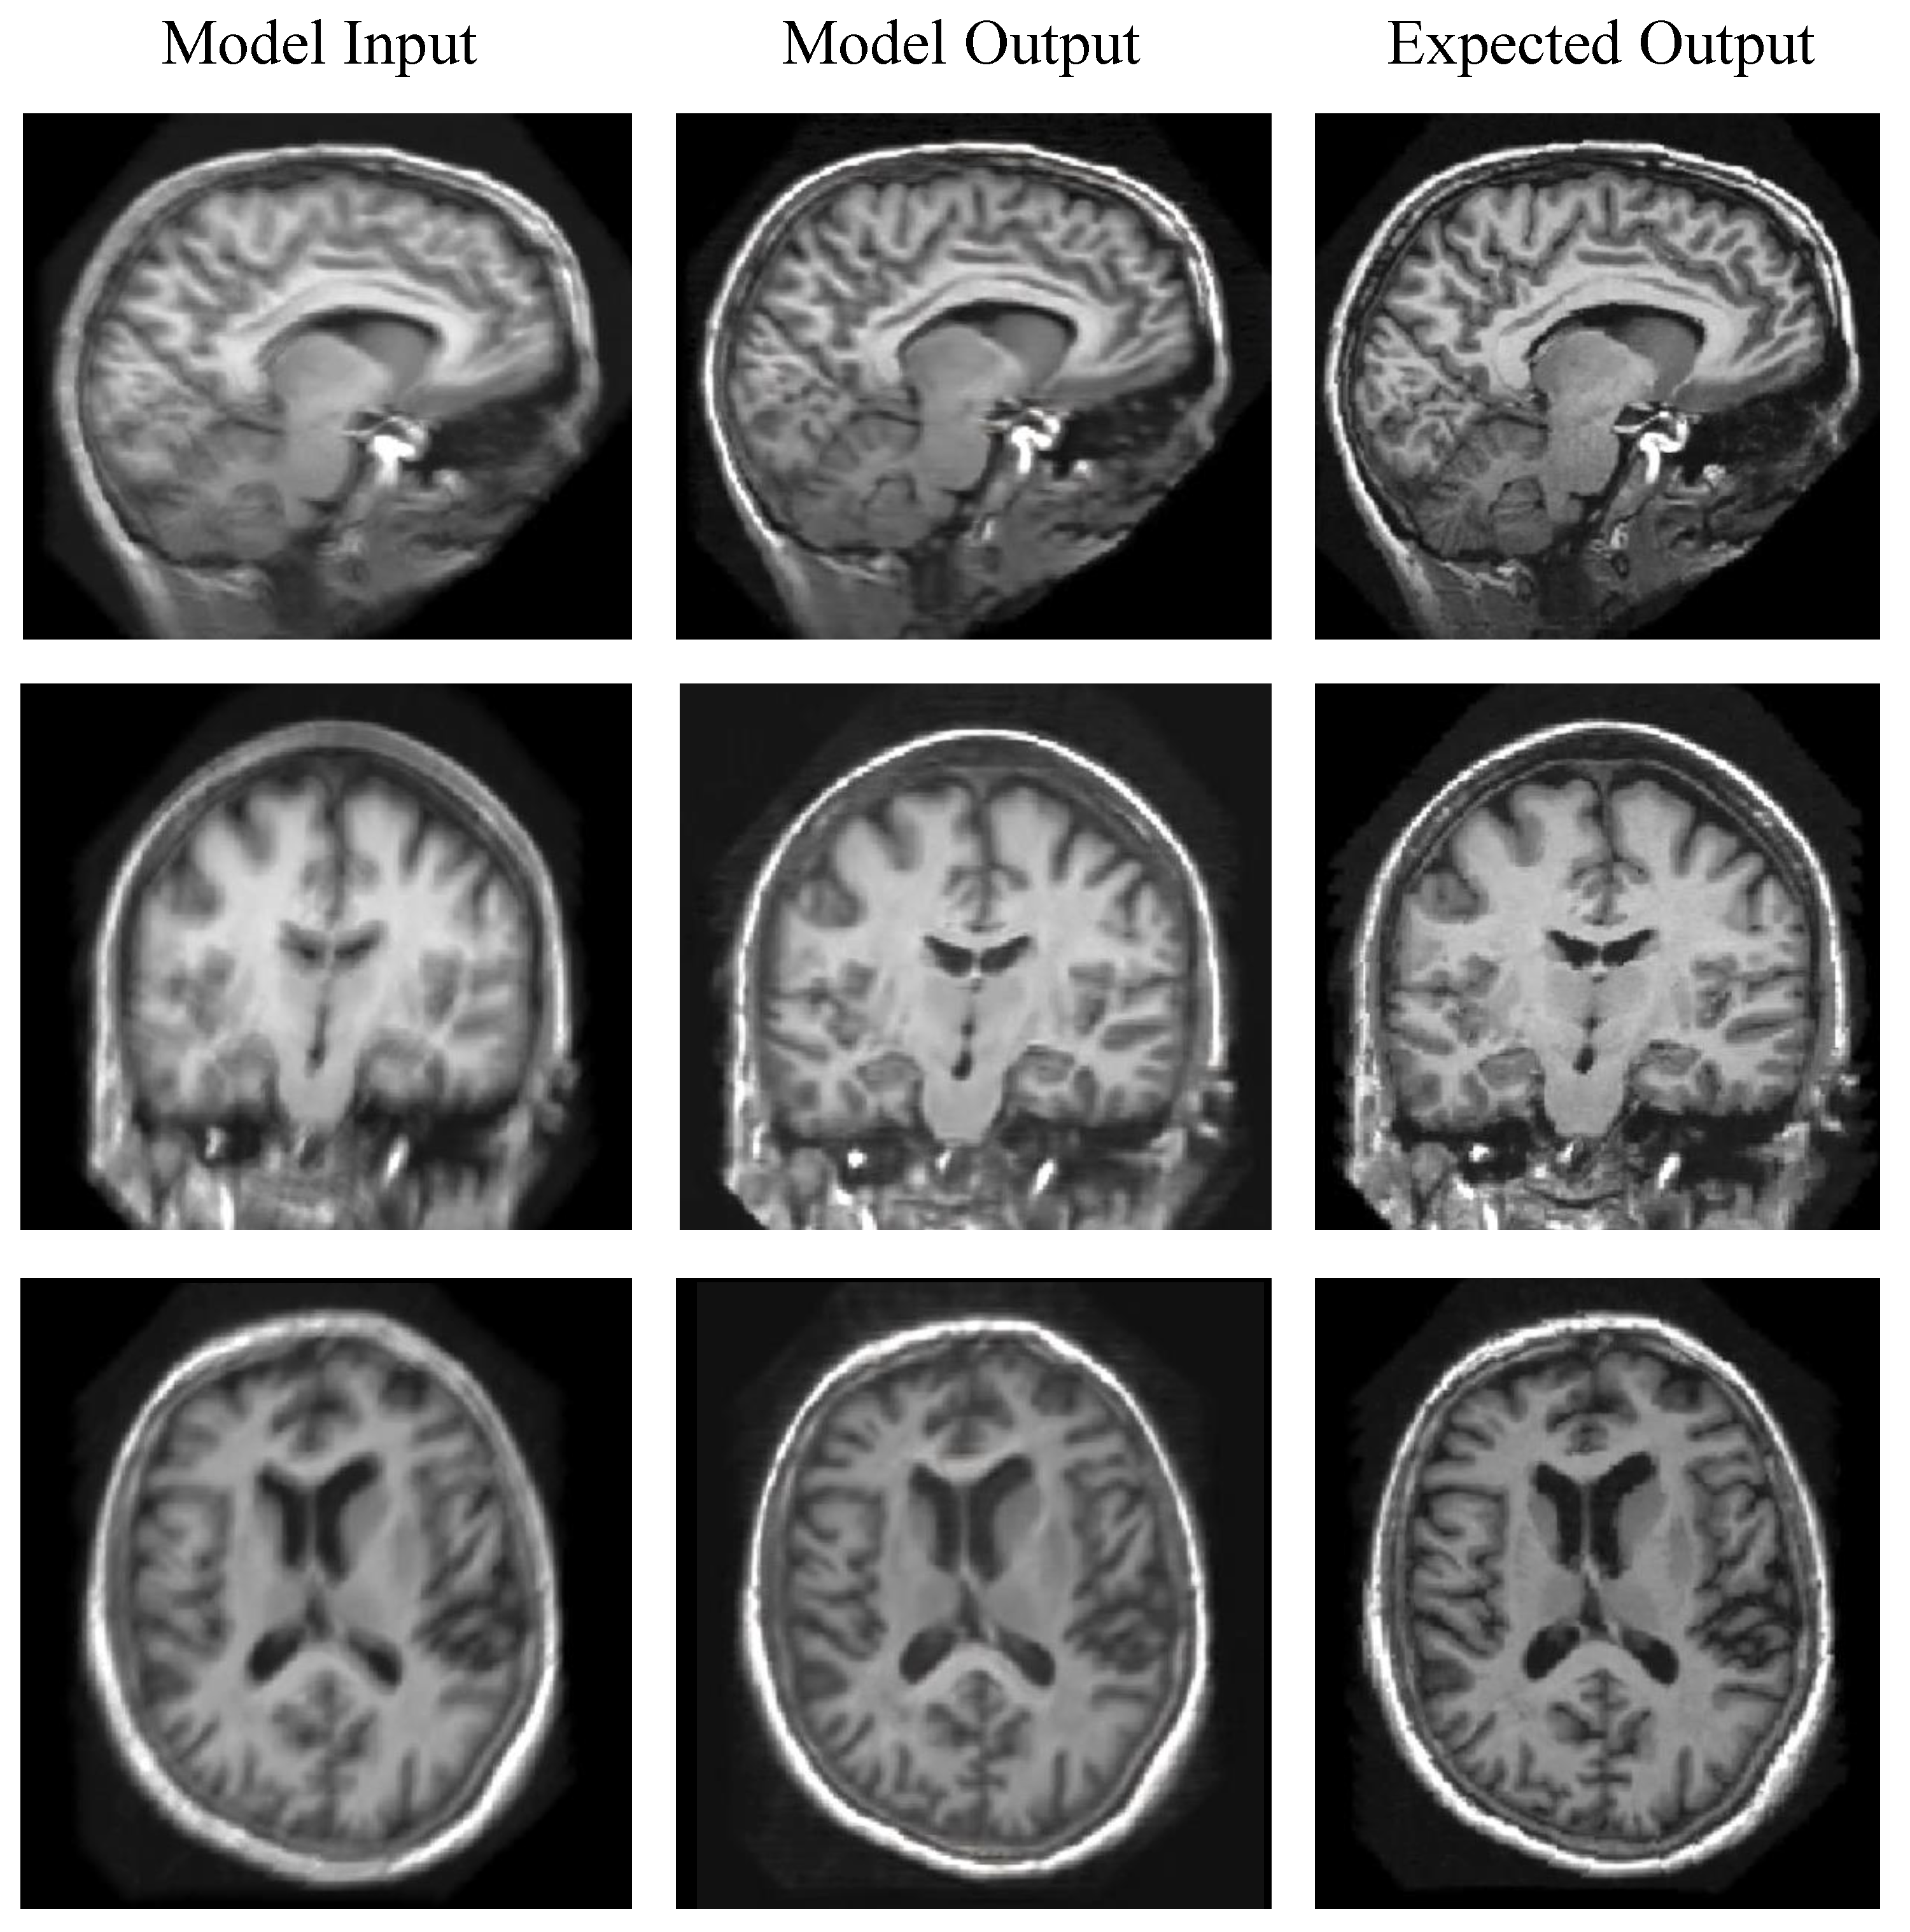

Evaluation on Synthetic Images